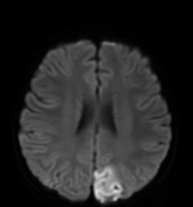

答:確診主要依靠頭顱磁共振檢查。引起兒童腦梗死的原因多樣,某些原因還會誘發(fā)腦梗死的復(fù)發(fā),因此對于腦梗死的患兒需進(jìn)一步評估有無心臟、血管及血液系統(tǒng)的其他危險因素。